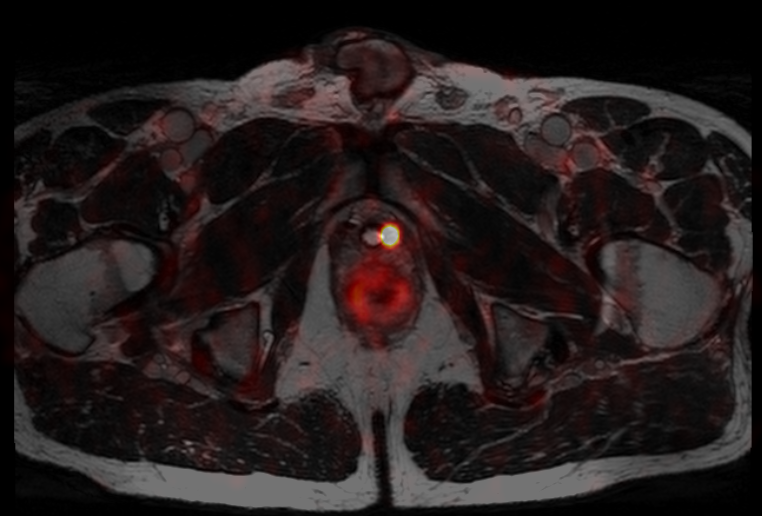

Prostate cancer - MR and PET imaging in personalized prostate cancer management

MR Cancer prostate image